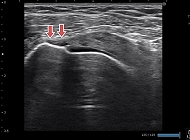

前距腓靱帯損傷

レントゲンでは評価できない靭帯損傷の有無、ゆるみの状態がわかります。